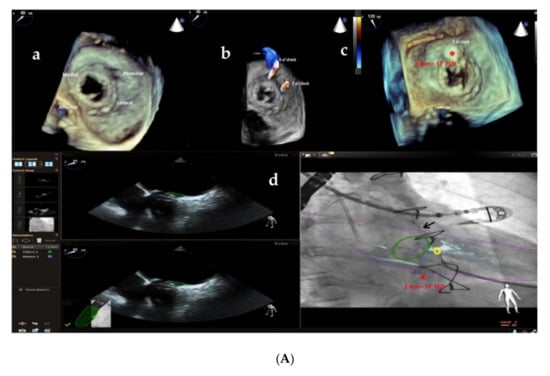

Furthermore, the use of multi-modality imaging such as fusion of real-time 3D TEE and cardiac fluoroscopy imaging has been shown to improve the safety and efficacy of percutaneous Mi and Ao PVL closure, facilitating catheter and guidewire access through the leaks by target markers [29] (Figure 7A,B; Supplementary Videos S1 and S2), reducing procedural time and radiation exposure.

Figure 7.

(A) Baseline 3D TEE color Doppler showing two round-shaped mitral PVLs with significant regurgitant jets located at 5 o’clock (3.2 mm) and 7 o’clock (3.6 mm) (a,b) in a female patient with a mitral bioprosthetic valve replacement; (c): successful implantation of a 3 mm-square twist PLD (red asterisk) at 5 o’clock; (d): fusion of real-time 2D TEE (Phillips Epiq7) and cardiac fluoroscopy imaging was obtained using EchoNavigator®-system (Philips Healthcare, Best, The Netherlands) with the fused image maintained demonstrating the location of the postero-laterally located (7 o’clock) mitral PVL (yellow circle) that was marked to aid the pathway of the guidewire (black arrow) crossing the leak, particularly in the case of a radiolucent bioprosthetic valve like in our patient. “*” refers to 3 mm-square twist PLD. (B) Intraprocedural navigation using fusion of 3D TEE and fluoroscopy with the fused image maintained helped the interventionalist to close successfully the second leak with a 5 mm-square twist PLD (black asterisk), improving the safety and the efficacy of this technically challenging procedure. PLD, Occlutech Paravalvular Leak Device ST, square twist, “*” refers to 5 mm-square twist PLD.